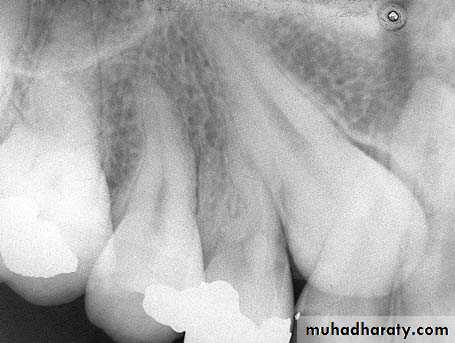

• Evaluation with a periapical radiograph is indicated and can illustrate the lack of a well defined periodontal ligament and lamina dura space and fusion of the root with bone.